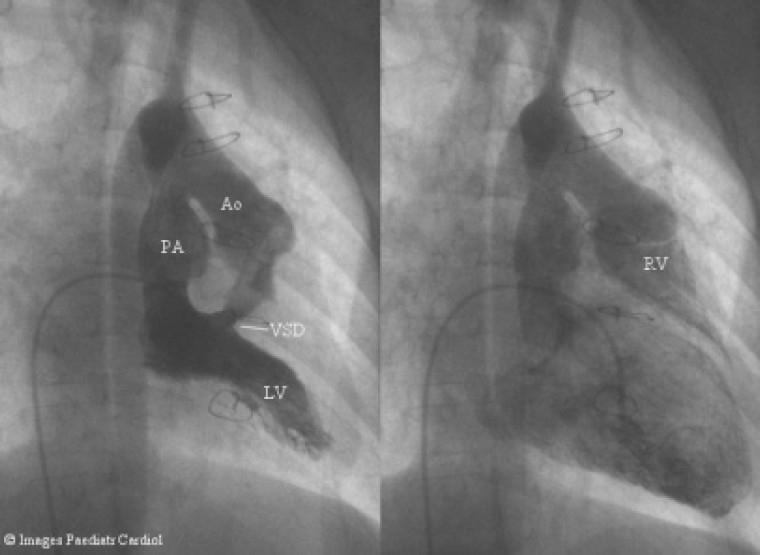

全腔静脉肺动脉连接术前先天性心脏病的心脏导管评估

Cardiac catheter assessment of congenital heart disease prior to total cavopulmonary connection.

This paper summarises the rationale behind cardiac catheter assessment prior to surgical completion of the Fontan circulation in hearts with univentricular pathology.

摘要